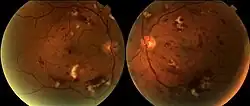

Radiation retinopathy is damage to retina due to exposure to ionizing radiation. Radiation retinopathy has a delayed onset, typically after months or years of radiation, and is slowly progressive. In general, radiation retinopathy is seen around 18 months after treatment with external-beam radiation and with brachytherapy. The time of onset of radiation retinopathy is between 6 months to 3 years.[2]

Clinically, affected people may not have symptoms or may complain of decreased visual acuity. Ophthalmic examination may reveal signs of retinal vascular disease, including cotton-wool spots, retinal bleeds, microaneurysms, perivascular sheathing, capillary telangiectasis, macular edema, and disc edema. Capillary non perfusion, documented by fluorescein angiography, is commonly present, and extensive retinal ischemia can lead to neovascularization of the retina, iris, and disc. Staging of radiation retinopathy has been proposed.[3]